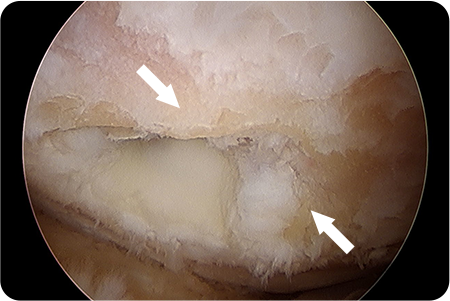

1. 관절내시경 삽입

무릎 관절 내부를 직접 확인하며 손상된 연골 부위를 관찰합니다.